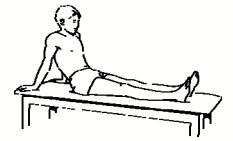

Ενδυνάμωση τετρακεφάλων Σφίξτε τους μυς που βρίσκονται πάνω από το γόνατό σας πιέζοντας το πίσω μέρος των γονάτων σας στο κρεβάτι. Η πτέρνα θα πρέπει να σηκώνεται από το κρεβάτι. Τυχόν νάρθηκες μπορούν να παραμείνουν. Μείνετε για 10 δευτερόλεπτα. Επαναλάβετε 10 φορές, 3 φορές ημερησίως.

Ενδυνάμωση του γονάτου

Ενδυνάμωση του γόνατος ενώ στέκεστε και κάμψη του ενός γόνατος

Σταθείτε ευθυτενείς στο πόδι που πονάει στην άκρη ενός σκαλιού και χρησιμοποιήστε μια καρέκλα για να στηρίζεστε. Λυγίστε το πονεμένο πόδι σας και σιγά-σιγά χαμηλώστε το άλλο πόδι κάτω από το ύψος του σκαλιού. Κανονικά πρέπει να αισθανθείτε ένα ελαφρύ τέντωμα στους μυς του γόνατός σας. Το χαμήλωμα πρέπει να διαρκέσει 3-5 δευτερόλεπτα. Το γόνατό σας πρέπει να είναι στραμμένο μπροστά.

Παραμείνετε σε αυτή τη θέση για 2 δευτερόλεπτα και επαναλάβετε την άσκηση 10-15 φορές 2 φορές την ημέρα. Με τις παραπάνω μεθόδους θα ανακουφιστείτε από τον πόνο στο γόνατο!

Ασκήσεις με βάρος Δοκιμάστε αυτές τις ασκήσεις όσο σας το επιτρέπει ο πόνος, μία εβδομάδα περίπου μετά τον τραυματισμό Σηκωθείτε στις μύτες των ποδιών σας. Επαναλάβετε 10 φορές, 3 φορές ημερησίως.